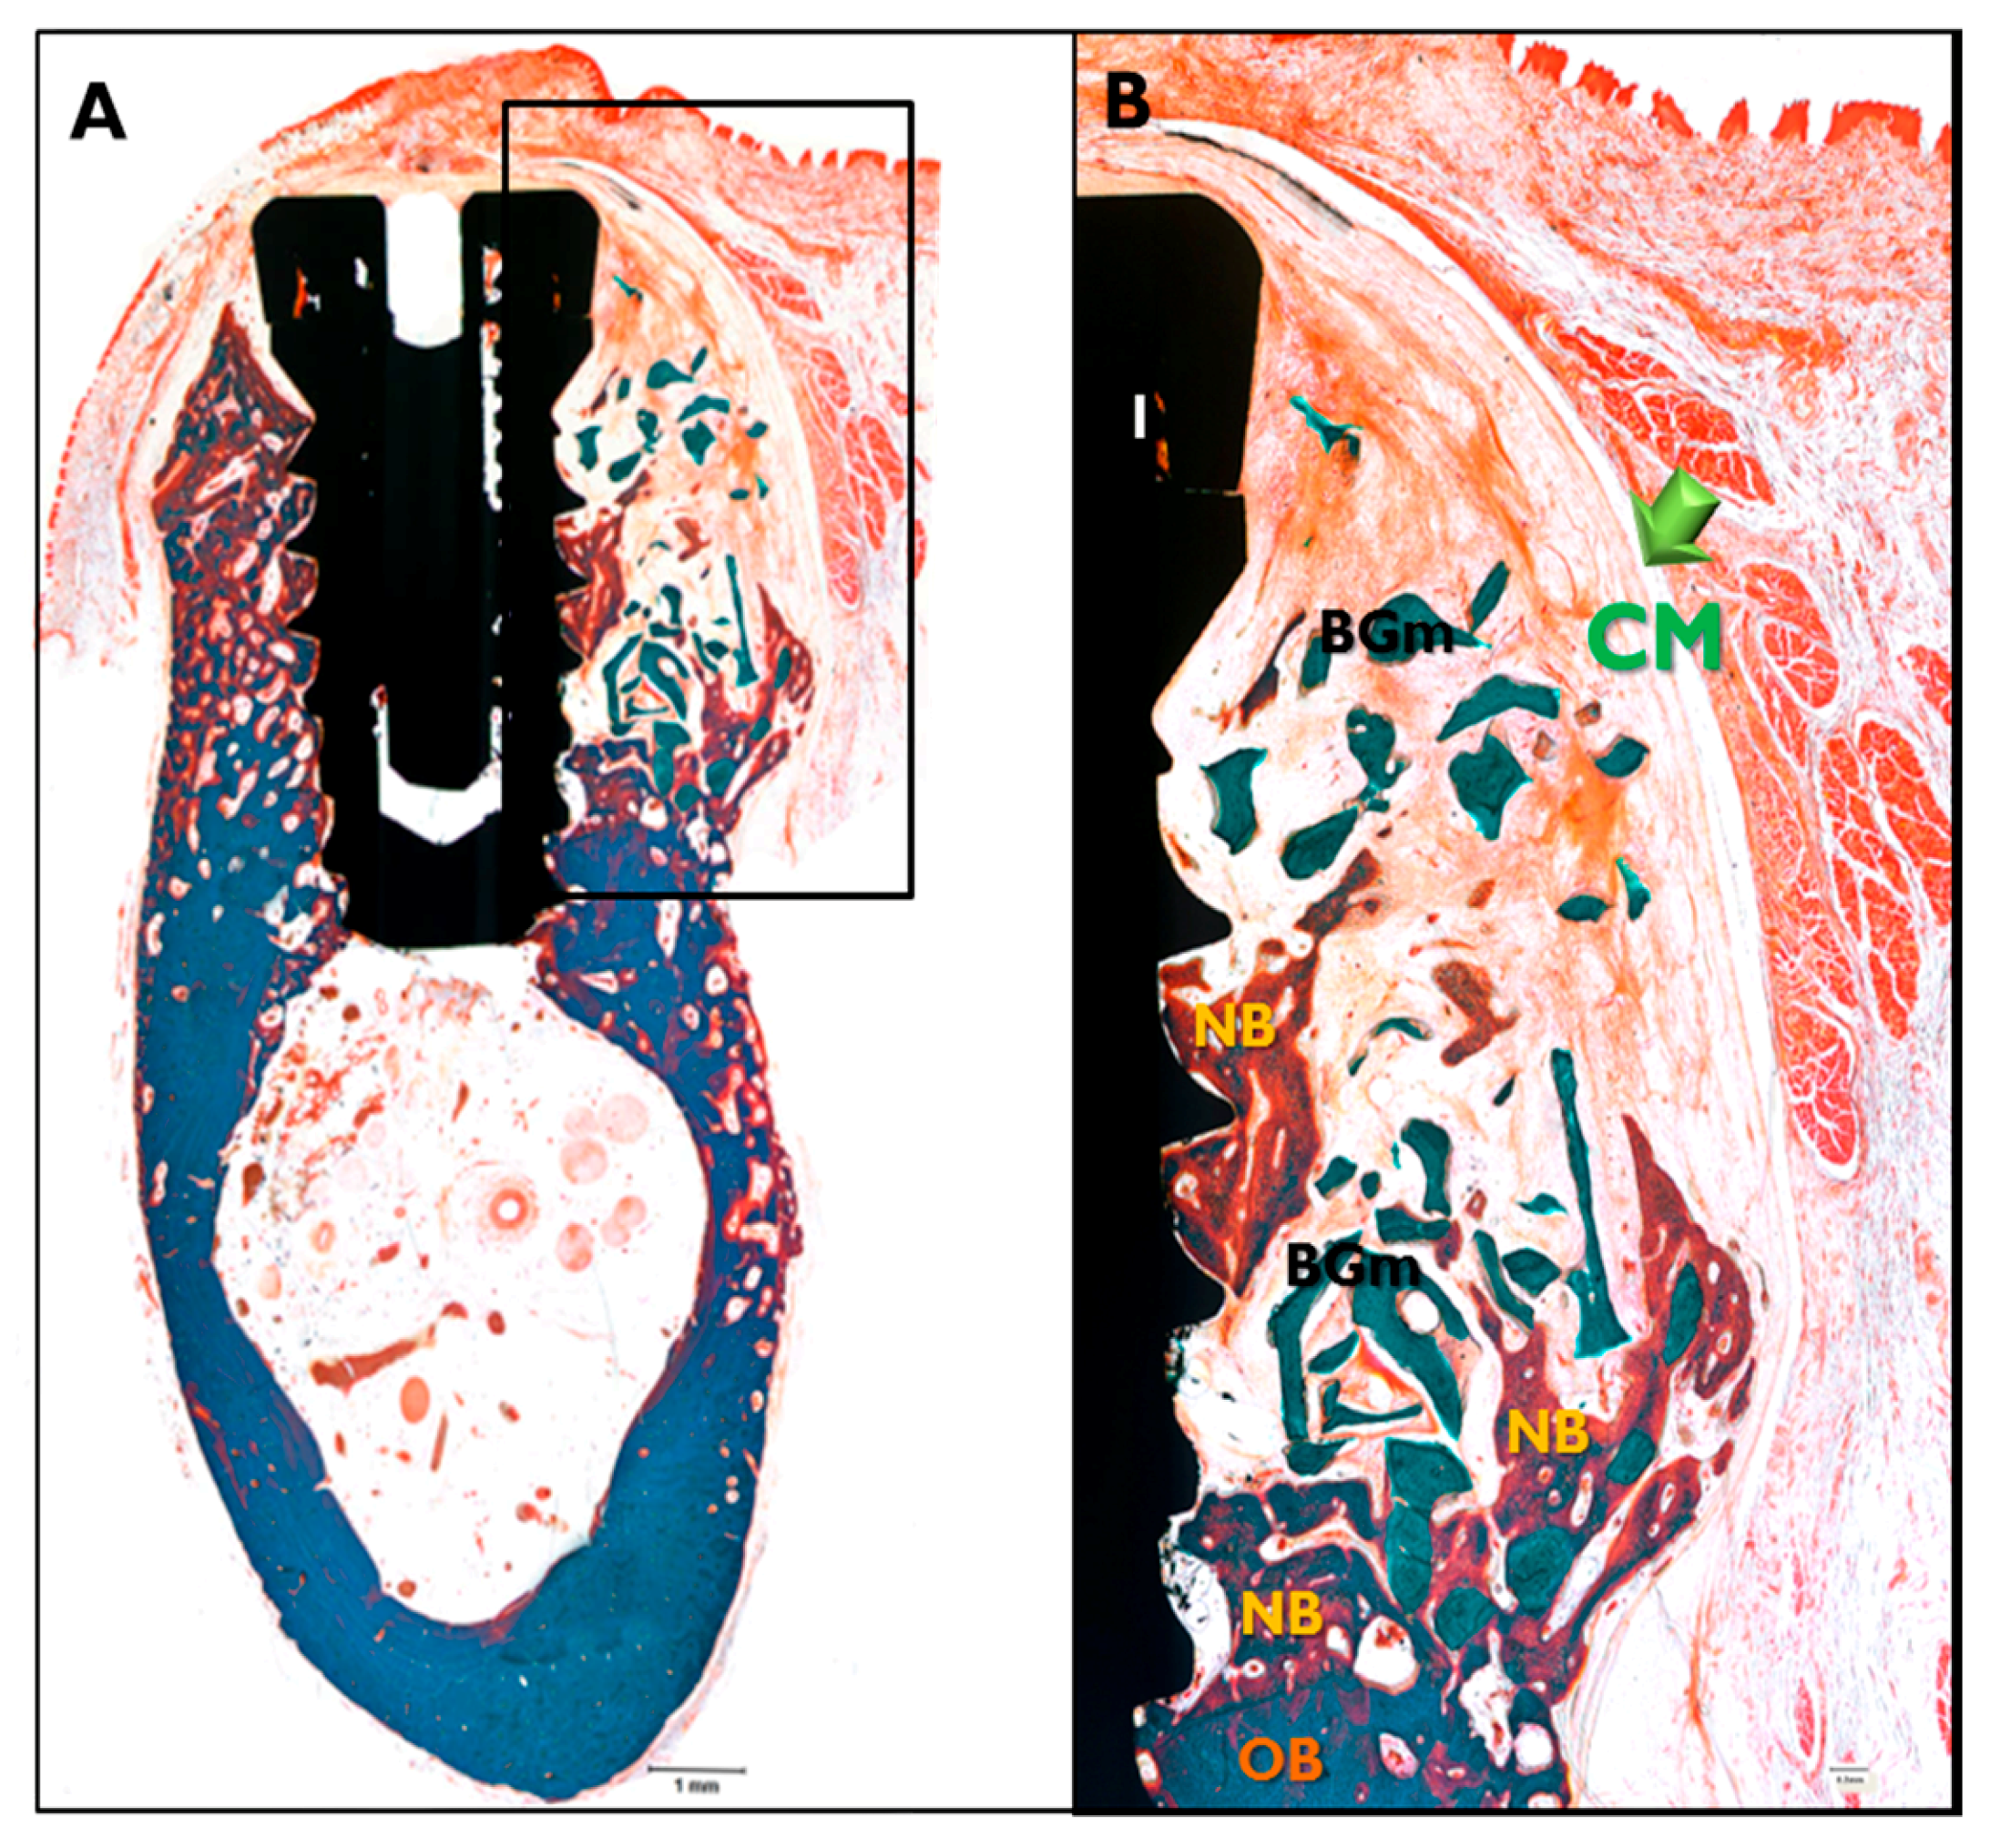

In the CM transplanted animals (Figure 8), a new bone formation was observed and fibrous connective tissues and graft materials were also observed in buccal peri-implant dehiscence defect areas. In some specimens, small amounts of membranes were observed. In the EI-BCM and CM transplanted animals (Figure 9), new bone, fibrous connective tissue, and graft materials were observed in the peri-implant dehiscence defect area. The EI-BC membranes remained at eight weeks in a similar pattern to the CM group, but expansion of the membrane was observed in some specimens.

Figure 8.

Histological sections specimen in CM transplanted animals. NB, new bone; BGm, bone graft material; OB, old bone; I, implant (Goldner Trichrome stained; original magnifications: 12.5× (A); and 40× (B)).